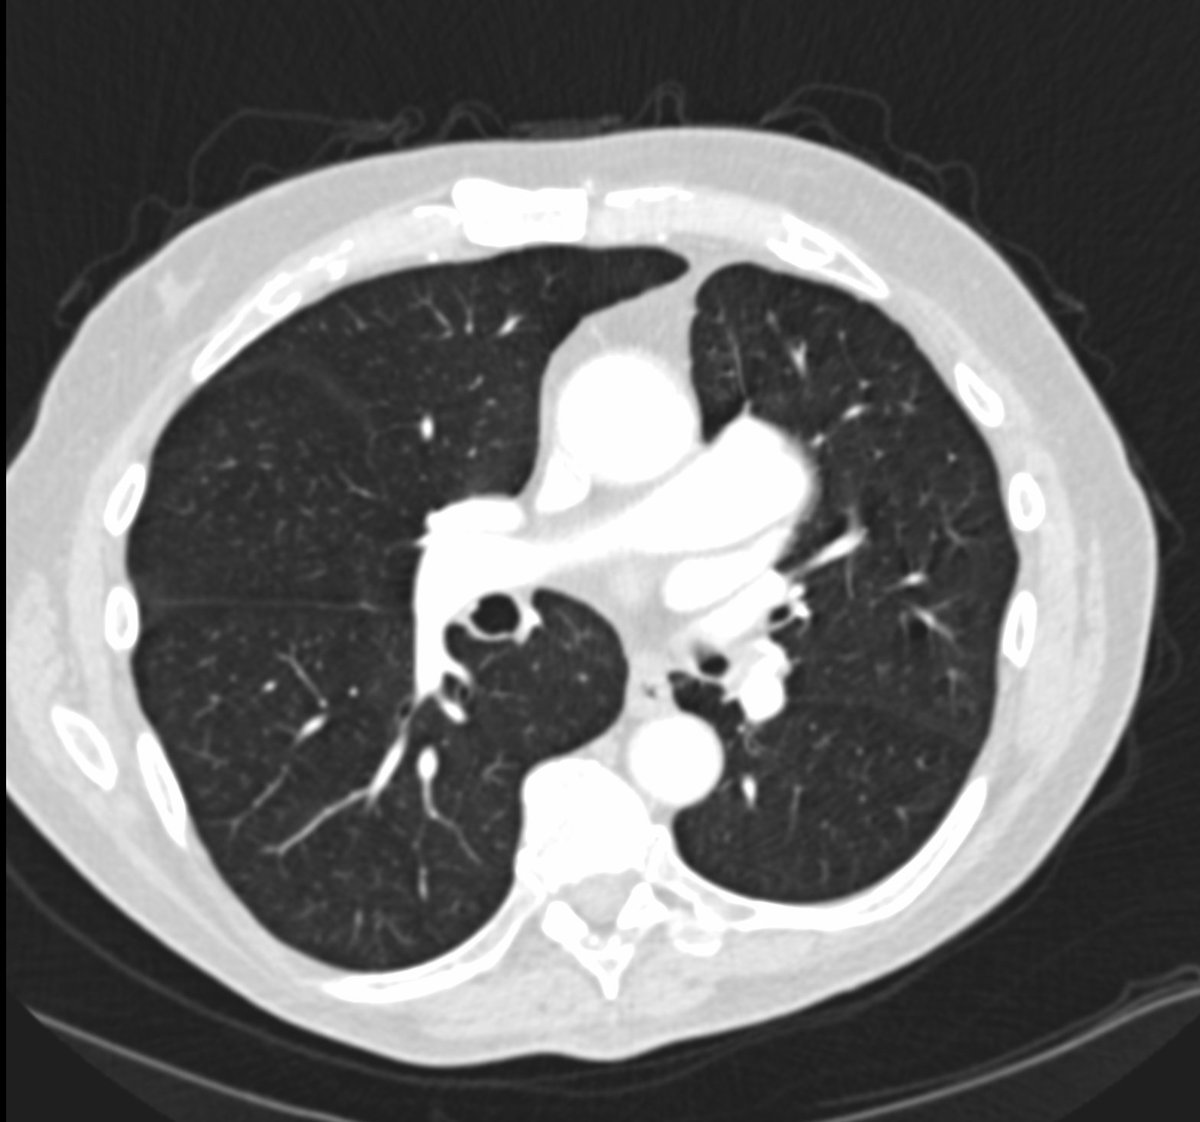

Friday conundrum. Routine chest radiograph and subsequent CT Thorax. Can you see anything abnormal on these images? Can you put it all together? Answers tomorrow.

#FOAMrad#FOAMed#FRCR#radiology#radiologists#CardioEd#cardiotwitter#RadRes#RadReg#meded Have a good weekend! pic.twitter.com/bkLPj1BPTa